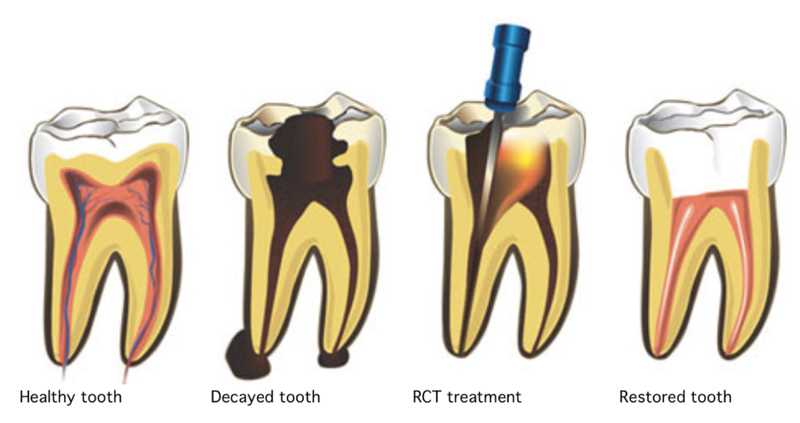

Root canal treatment

We do painless and effective root canal treatment in our practice.